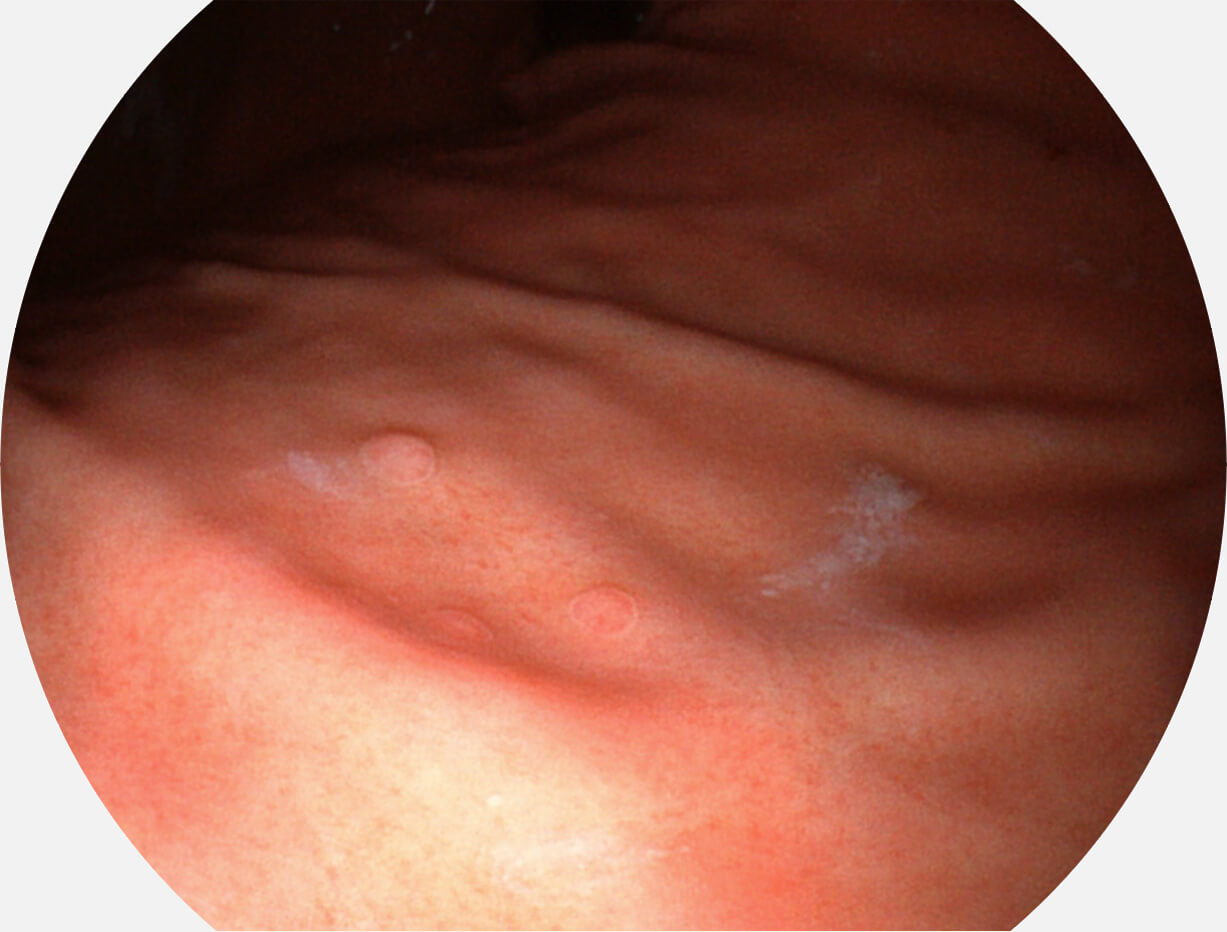

强调浅层黏膜结构的同时,保证照明亮度和提升浅层微血管与中层血管颜色对比度,病变边界更清晰。

• 白光图像 VIST图像